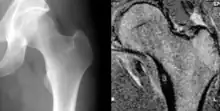

Osteoid osteoma of the lesser trochanter: X-ray and MRI with marked sclerosis around the nidus | |

Radiographs in osteoid osteoma typically show a round lucency, containing a dense sclerotic central nidus (the characteristic lesion in this kind of tumor) surrounded by sclerotic bone. The nidus is seldom larger than 1.5 cm.

The lesion can in most cases be detected on CT scan, bone scans and angiograms. Plain radiographs are not always diagnostic. MRI adds little to the CT findings which are useful for localisation. Radionuclide scanning shows intense uptake which is useful for localisation at surgery using a hand held detector, and for confirmation that the entire lesion has been removed.[8][9]